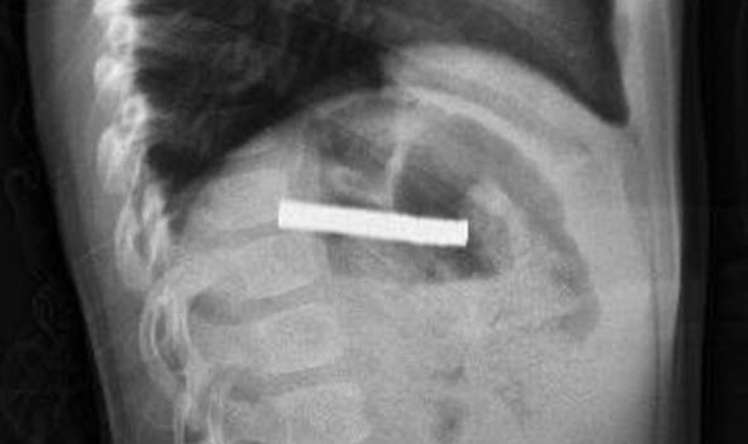

Vərəm – çox ağır infeksion xəstəlikdir. Öskürək xroniki olur, heç bir dərman, türkəçarə saxlamır, uzun müddət davam edir. Metallik səs verir. İlk başda quru ola bilir, sonra yaşa çevrilir. Ən təhlükəli siqnalı bəlğəmdə qan olmasıdır. Xəstə gecələr tərləyir, halsız olur, sürətlə arıqlayır.